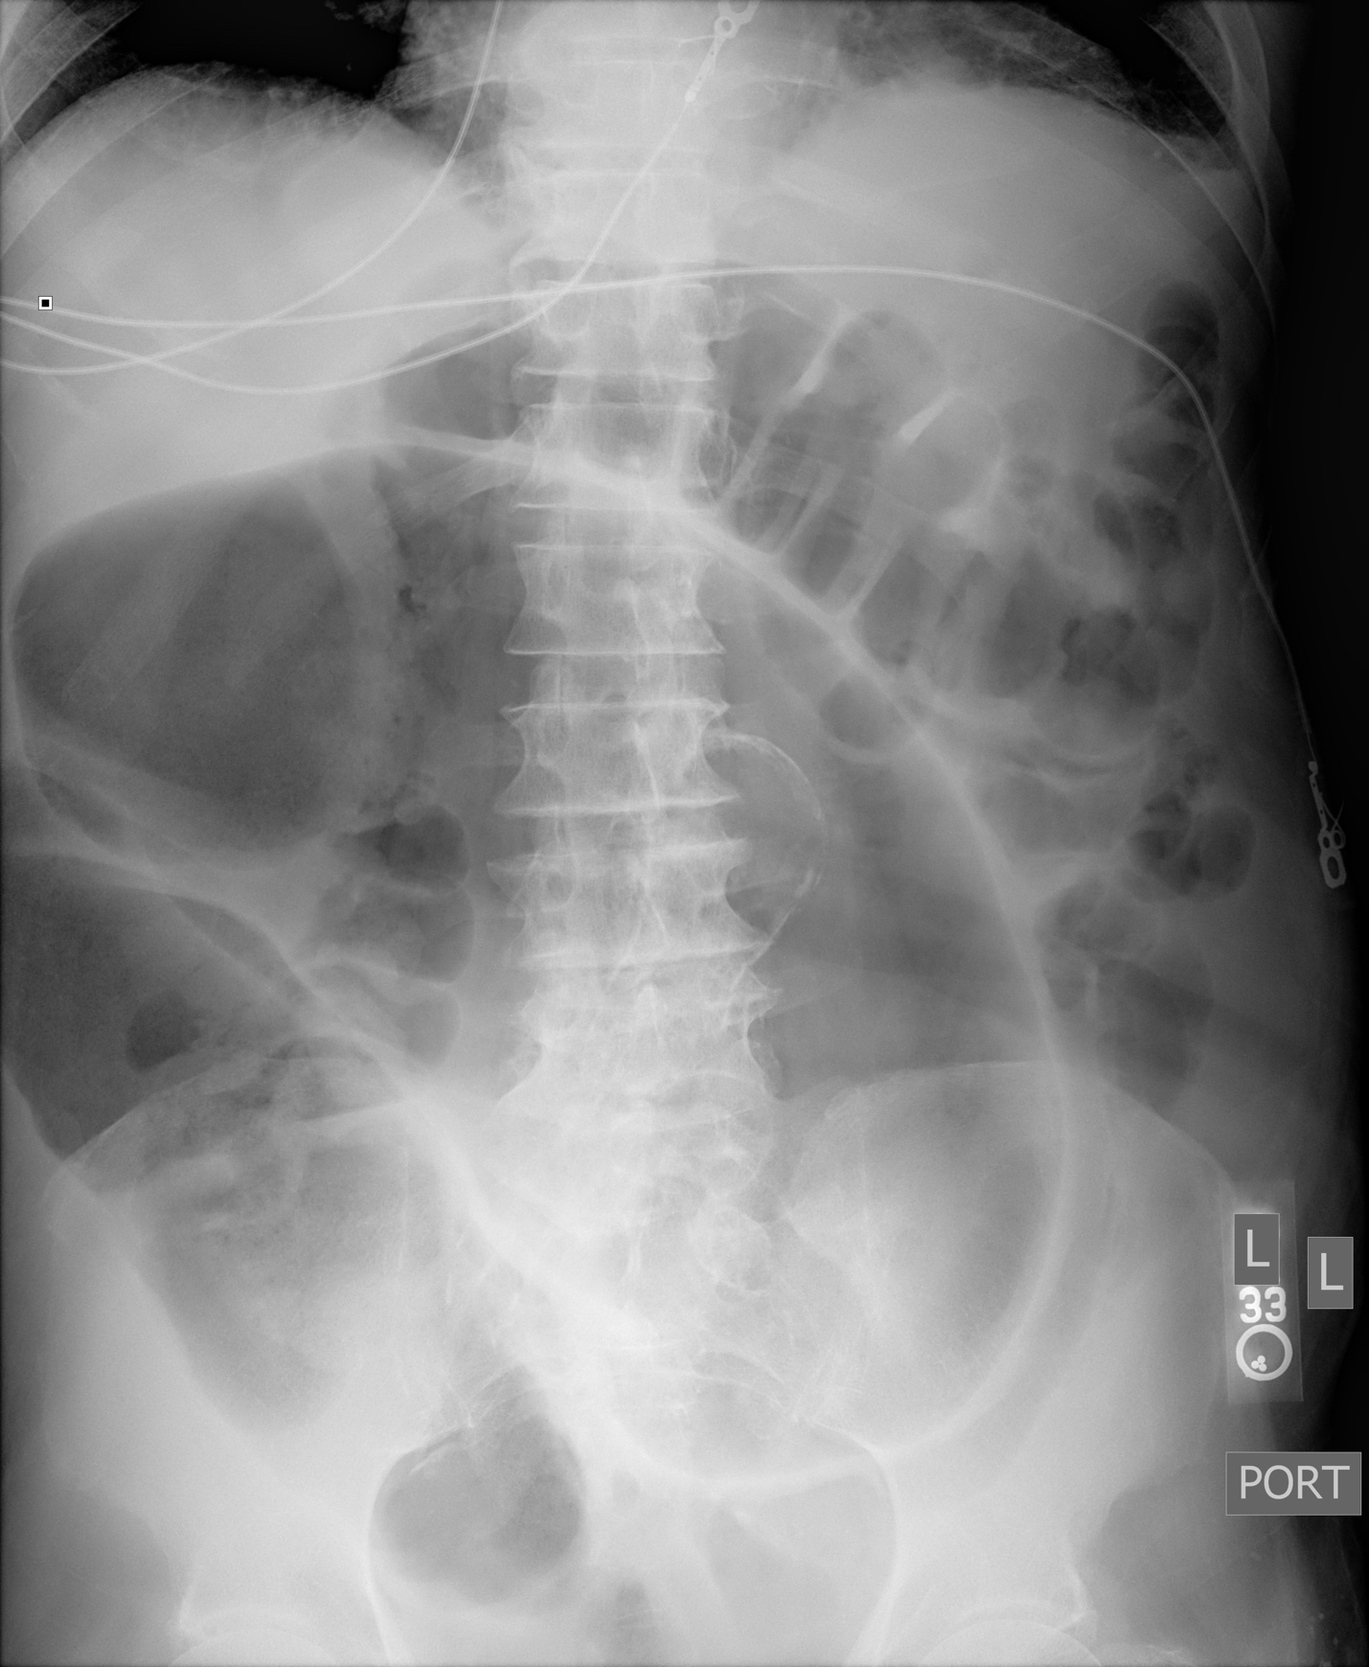

A 99-year-old man presented to the hospital with four days of progressive abdominal pain and distention accompanied by anorexia and obstipation. Examination revealed a markedly distended, tympanitic abdomen with hypoactive bowel sounds and diffuse tenderness. An abdominal radiograph showed markedly dilated loops of large bowel shaped like a coffee bean (Figure 1). Computed tomography (CT) of the abdomen and pelvis confirmed a severe dilation of the sigmoid colon with twisting of the sigmoid mesocolon and vessels consistent with sigmoid volvulus (Figure 2). The patient underwent flexible sigmoidoscopy for endoscopic decompression and ultimately required colectomy for recurrent sigmoid volvulus.

The “coffee bean sign” is a conventional radiographic finding classically associated with the closed loop bowel obstruction in sigmoid volvulus. In sigmoid volvulus there are often multiple dilated loops of large bowel present as adjacent air-filled densities with an inner wall created by two layers of bowel wall abutting one another.1 Often caused by anatomic variations and redundant sigmoid colon, patients at particular risk for sigmoid volvulus include older male patients, nursing home residents, and those with chronic constipation, neurologic disease, and prior abdominal surgery.2 As sigmoid volvulus may quickly lead to bowel infarction and necrosis, timely recognition and distinguishing from mimics such as acute colonic pseudo-obstruction (ACPO) is essential.